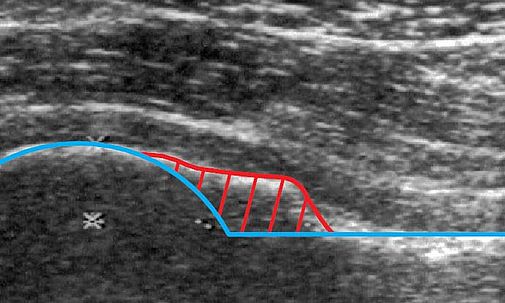

Abb.: Sonografie: CAM-Impingement (rot), Idealkontur (blau)

Bei der Untersuchung zeigt sich meist eine verminderte Innenrotation des betroffenen Beins, die meist seit der Jugend bekannt ist und mit der Zeit zugenommen hat. Durch eine Ultraschall-Untersuchung kann ein erster Verdacht auf ein FAI geäußert werden, der bei entsprechendem Befund durch eine Röntgenaufnahme bestätigt werden kann. Bei unklarem Befund kann zur Komplettierung der Diagnostik eine hochauflösende Kernspintomographie mit speziellen axialen Rekonstruktionen durchgeführt werden. Durch diese speziellen Rekonstruktionen lassen sich auch verdeckte Fehlbildungen darstellen. Bestätigt sich in der Bildgebung der Verdacht auf ein femoroacetabuläres Impingement und ist noch ausreichend Knorpelbeschichtung an den Gelenkpartnern vorhanden, so kann eine gelenkerhaltende Operation durchgeführt werden.